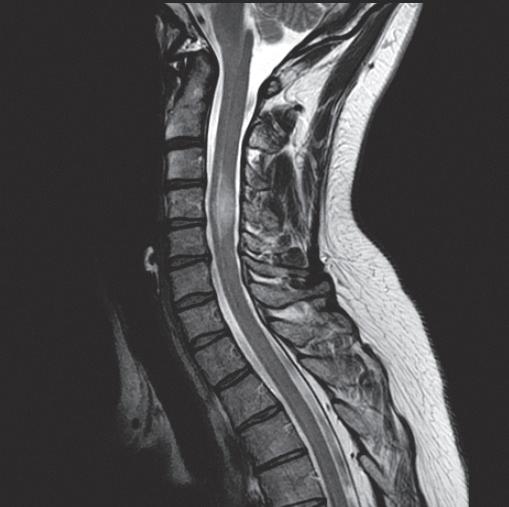

Fellows will participate in the care of patients with simple to complex spine challenges, with the goal of helping them safely return to their routine activities and workplaces, while preventing long-term disability from back and neck pain.

Fellows will work and train with team members from physical medicine and rehabilitation, family medicine, radiology, neurosurgery, orthopaedic surgery, pain psychology, and physical/occupational therapy; and they will observe a variety of spine care procedures –from ambulatory settings to the operating room – to prepare for practicing on a spine-focused team.